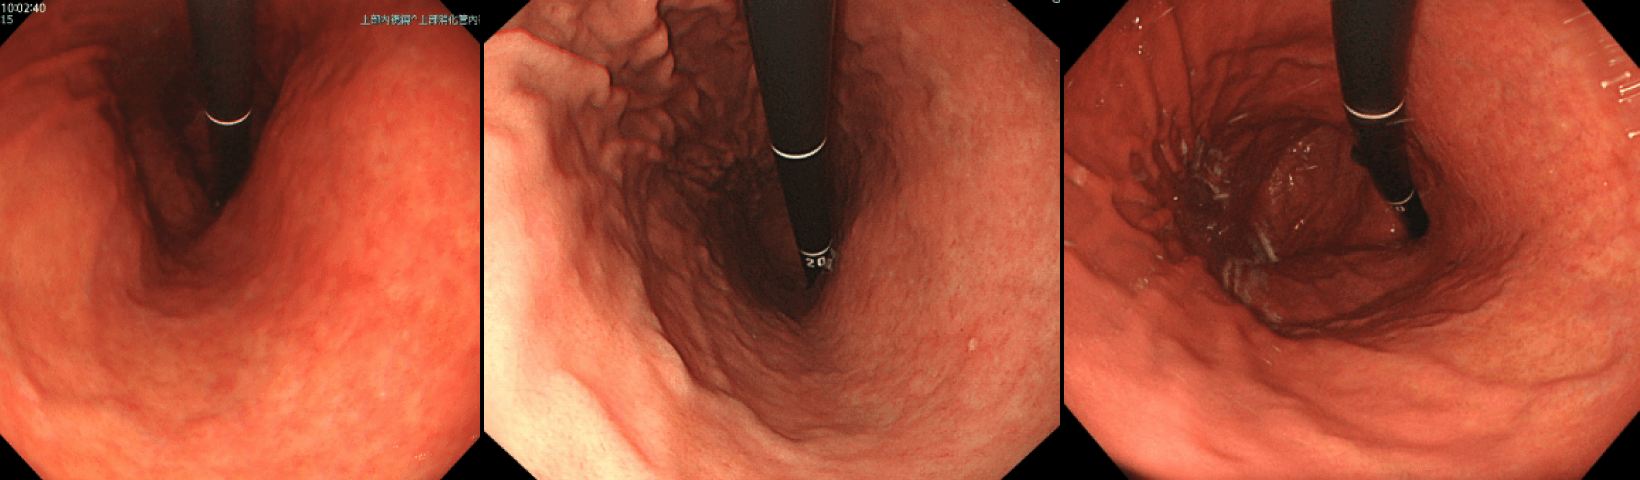

左:本体がオリンパスEVIS、右:本体がX1

上記写真はいずれも同一患者さんに対し1200Nという細径カメラでとったものです・右側のほうが胃の微細な粘膜模様がわかります。